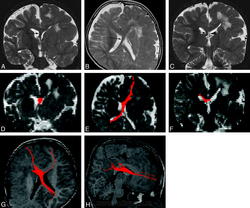

Диагноз ГМЭ в современных условиях устанавливается, в подавляющем большинстве случаев, при МРТ исследовании головного мозга. МРТ у больных с ГМЭ выявляет асимметрию гемисфер за счет диффузно увеличенного, аномального полушария. Характерна вентрикуломегалия диспластичной гемисферы. В Т2 - режиме выявляется интенсивный сигнал в белом веществе - результат сочетания глиоза и участков гипомиелинизации.